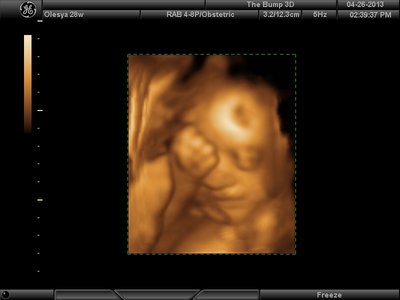

Еще одна, качество ужасное..

| Вложения: |

image.jpg [ 60.32 КБ | Просмотров: 1453 ]